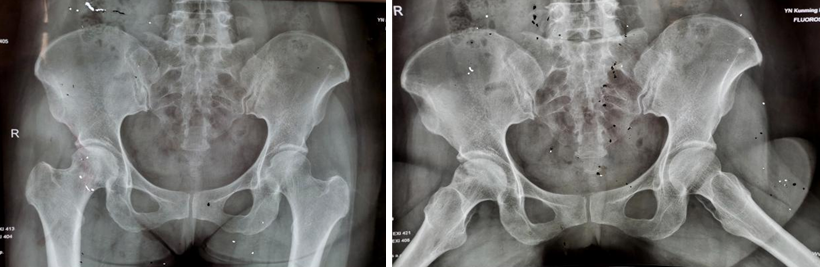

两年多前,34岁的王先生因双髋部疼痛伴活动受限4月余,在家人的搀扶下,一脸痛苦地来到樱花动漫 骨科就诊。杨振东副主任医师接诊了这位患者,该患者饮酒史10年,每日2两,戒酒1月,右髋外旋活动受限,左髋活动正常,右髋“4”字试验阳性,结合影像学资料显示,该患者右侧股骨头凹凸不平、黯淡无光,且有部分塌陷,诊断为右侧股骨头坏死。

术后12个月和24个月,患者来院复查,影像片子显示患者右侧股骨头髋臼平整光滑,股骨头圆润光滑,股骨头内骨小梁密度均匀,已恢复至正常股骨头状态,几乎与正常人股骨头无异。患者随访时说:“来医院之前,我独立行走都困难,短短几米的距离,我可能要花费三四分钟才能走完。手术之后,我不仅可以健步如飞,还能做下蹲等动作,也不必担心重体力劳动导致股骨头无法承受的问题,这个手术真的是太好了,不仅救了我,也救了我一家人……”